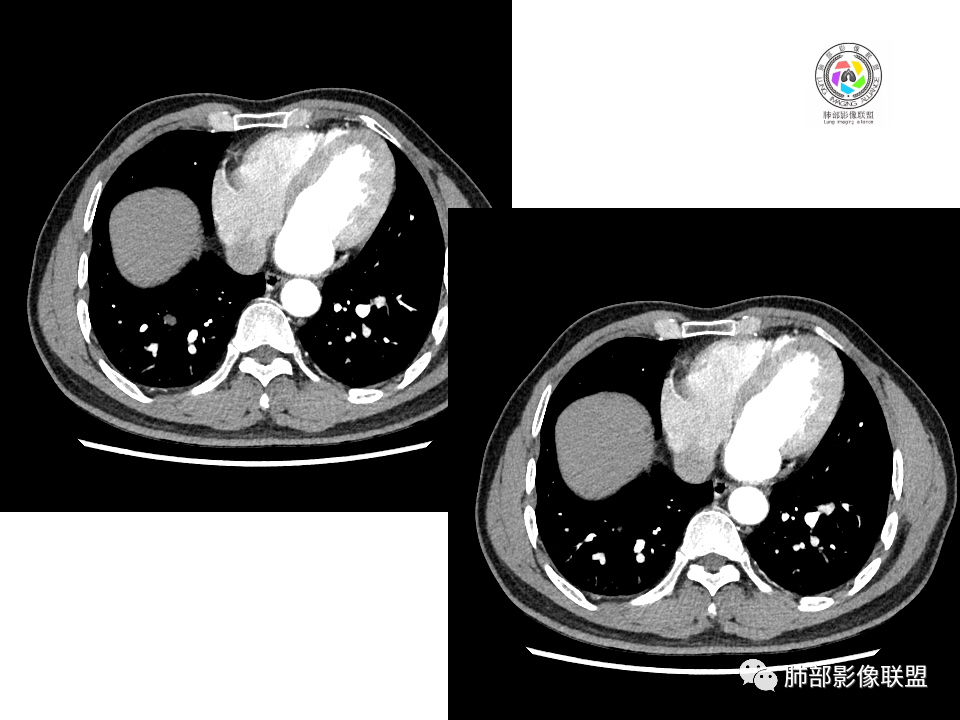

2.右肺下叶背段胸膜下块影,边界清楚光整,上下极见磨玻璃晕,未见明显分叶毛刺和棘状突起,未见胸膜凹陷或胸壁侵入。密度均匀,轻度不均匀强化。未见支气管进入。

3.右肺中叶外侧段胸膜下散在小片影,磨玻璃密度为主,边界不清,支气管相关。符合炎性特征!

4.右肺下叶基底段支气管血管束旁小结节影,边界清楚,强化不明显。注意,这结节在“遥远的”基底段。

右肺下叶占位,胸膜下,与胸膜关系密切;

密度均匀;糊墙,边缘膨隆为主;

部分血管推移。